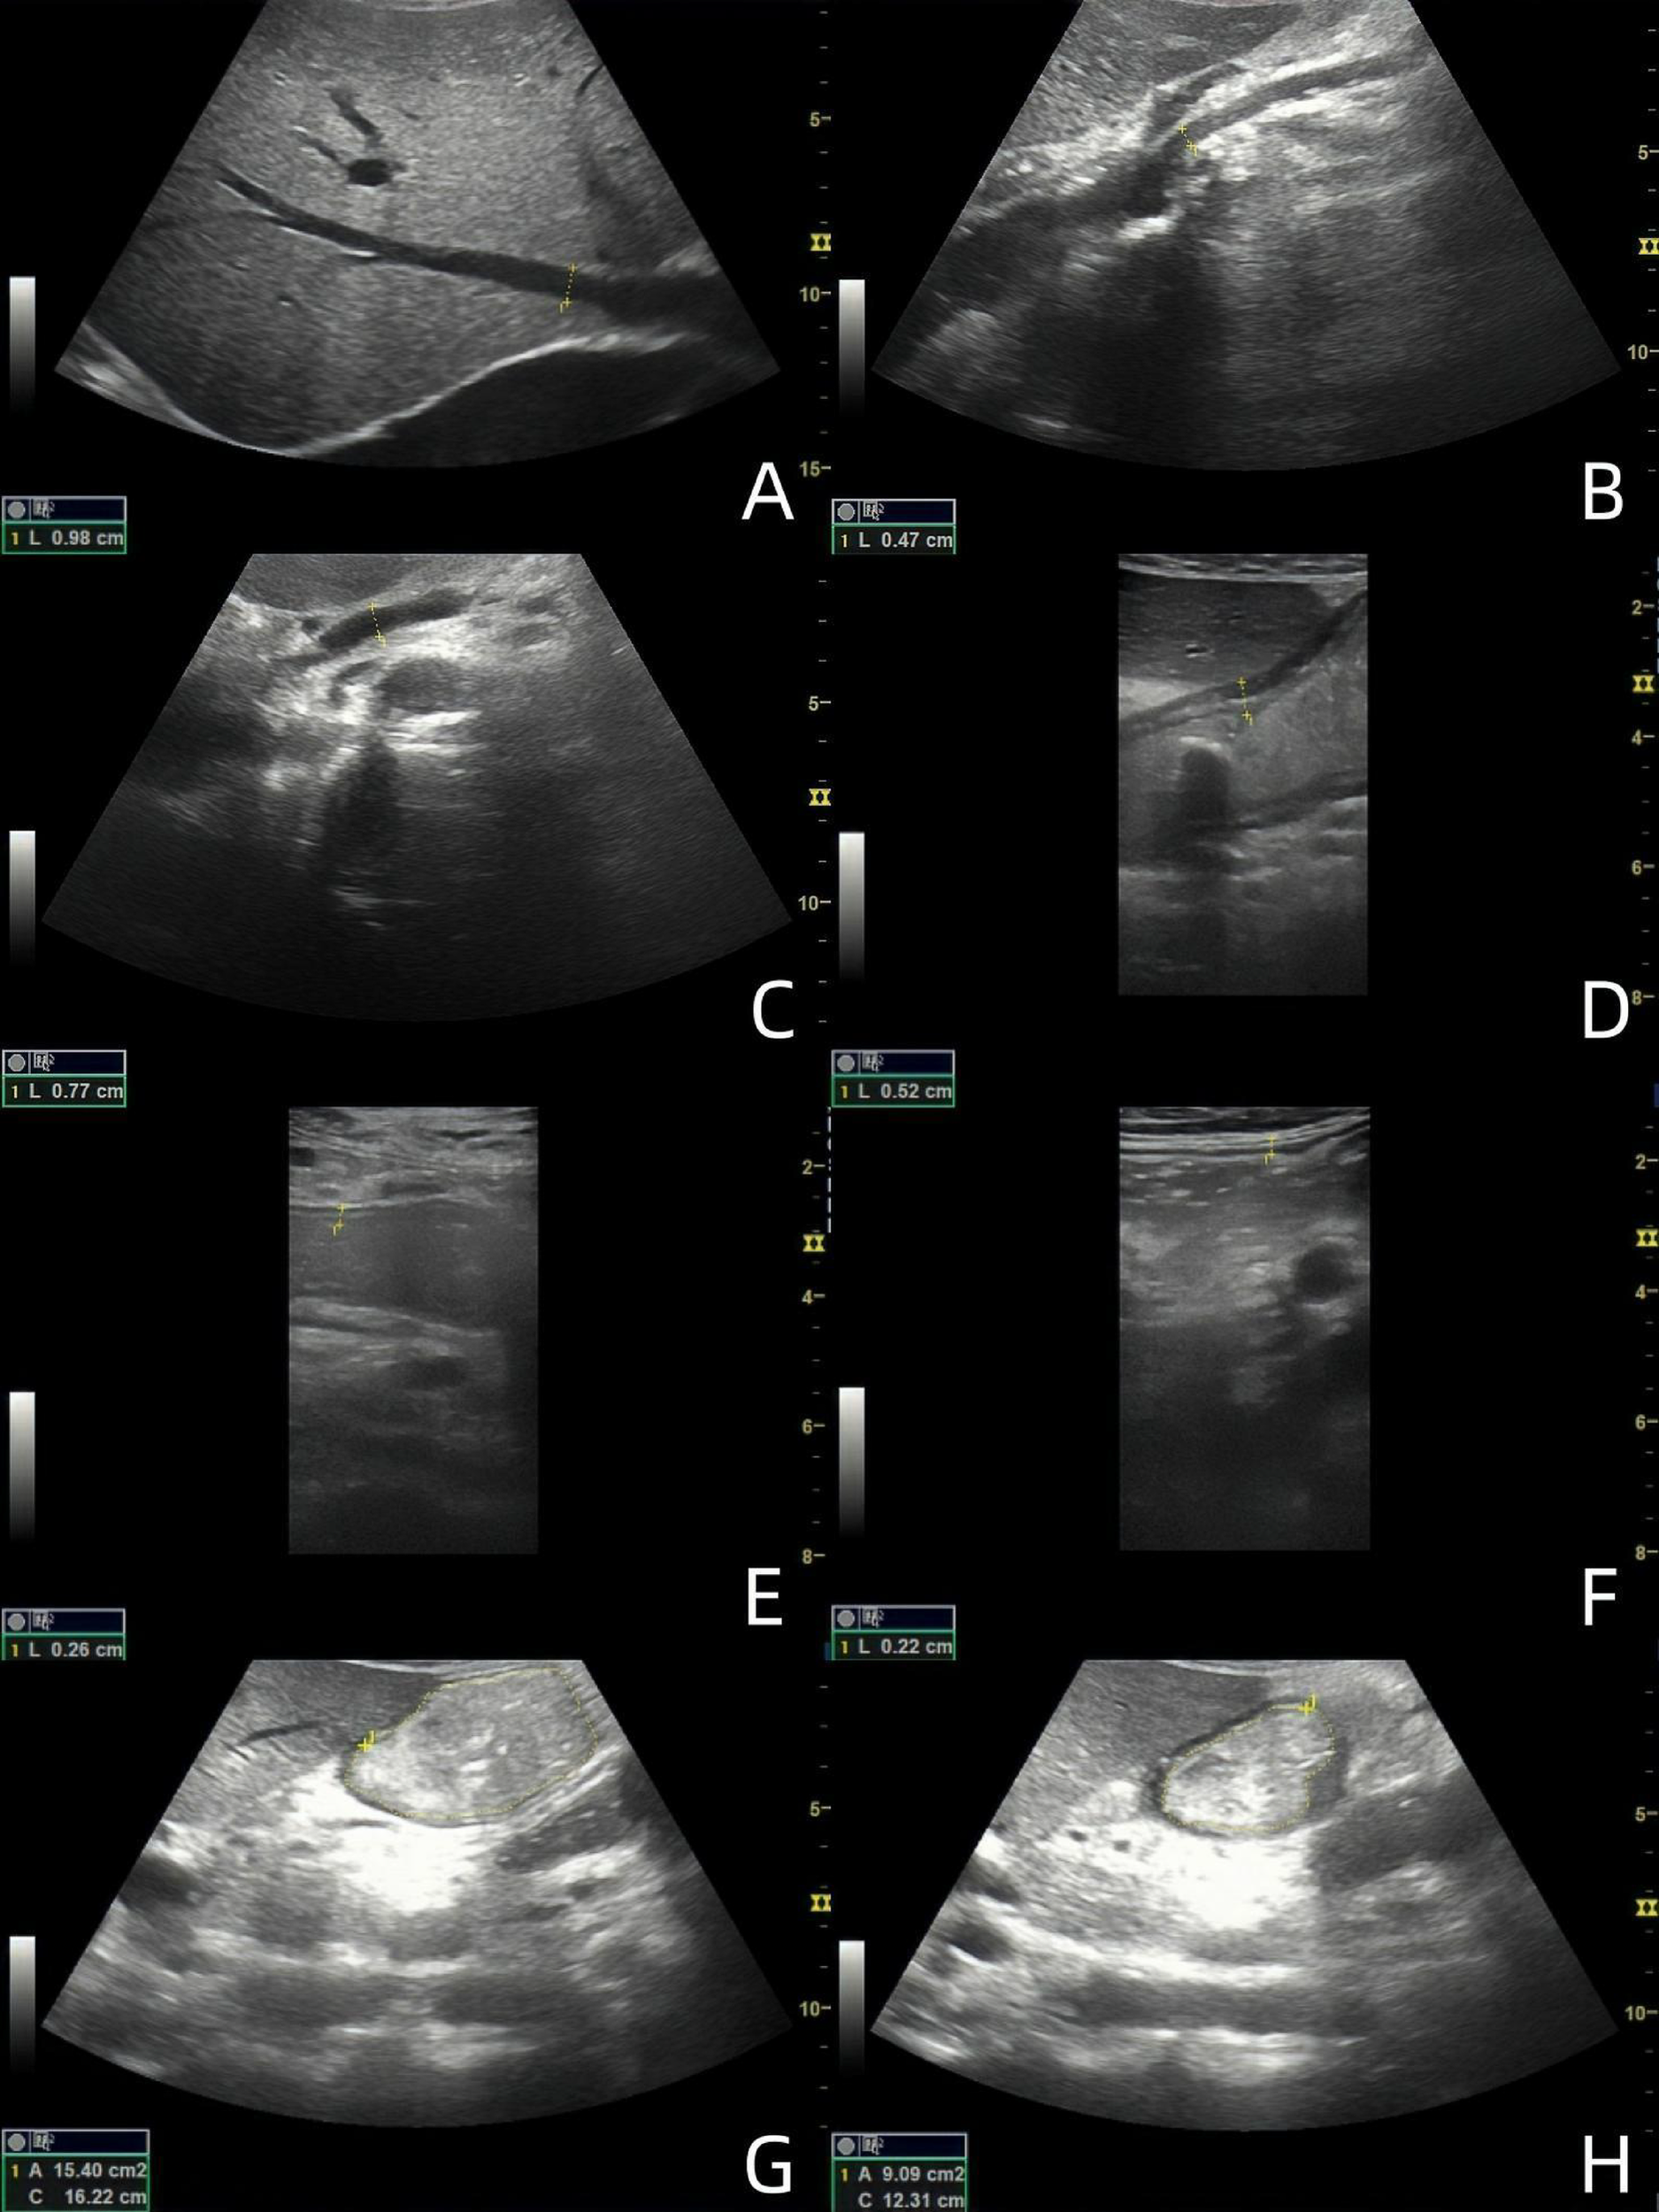

All subjects fasted for more than 6 h. The convex array probe was used to scan the abdomen of the subjects in both groups. First, three hepatic veins (HVs) were displayed, the image was appropriately enlarged, and the inner diameters of the three HVs were measured, with the maximum value recorded (Figure 1A). Subsequently, the superior mesenteric artery (SMA) and superior mesenteric vein (SMV) were displayed, and the image was enlarged appropriately to observe the lumen structure. The inner diameter was measured within 1 cm from the starting position (Figures 1B,C). Color Doppler imaging was performed to observe the blood flow filling, and spectrum Doppler imaging was performed to measure the peak velocity corresponding to the inner diameter measurement site.

Figure 1

Ultrasound images of 49-year-old male patients with acute heart failure. (A) Maximum diameter of hepatic vein; (B) SMA inner diameter; (C) SMV inner diameter; (D) antral wall thickness; (E) Jejunal wall thickness; (F) Ascending colon wall thickness; (G) Maximal diastolic area of gastric antrum; (H) Minimal contraction area of gastric antrum. (The images are sorted from left to right and from top to bottom as A-H).

The subjects were instructed to drink 300 ml of warm water while in a semi-recumbent position. The convex array probe was placed under the xiphoid process, and the probe marker oriented towards the subject's head to show the sagittal plane of the midline of the abdomen. The probe was slightly lateralized, and the gastric antrum, abdominal aorta, and SMA were displayed at the same time to evaluate the contraction of the gastric antrum (Figures 1G,H). The probe was stabilized 3 min to observe and calculate the contraction frequency per minute of the gastric antrum and to measure the antral contraction amplitude (ACA). ACA = (the maximum antral diastolic area - the minimum antral systolic area)/the maximum antral diastolic area. The motility index (MI) was then calculated as MI = Antral contraction frequency (ACF) (The number of antral contractions per minute) × ACA × 2 (6). The convex array probe was then moved to the umbilical level to display the long axis of the jejunum. The probe was observed for 2 min to calculate the peristaltic frequency of the jejunum per minute. The peristaltic frequency of jejunum = the number of jejunum peristalsis in 2 min ÷ 2. Subsequently, the convex array probe was moved to the right abdomen to display the ascending colon. The probe was stabilized for 2 min to calculate the peristaltic frequency of the ascending colon per minute. The peristaltic frequency of ascending colon = the number of ascending colon peristalsis in 2 min ÷ 2. The high-frequency linear array probe was then placed at the corresponding body surface positions of the gastric antrum, jejunum, and ascending colon, respectively. The images of the regions of interest were enlarged, and the wall thickness was measured from the hypoechoic layer of the muscularis propria to the hypoechoic layer of the mucosa. Measurements were taken as vertically as possible, avoiding colonic haustra and mucosal folds in the colon. Each measurement was repeated three times, and the average value was calculated (Figures 1D–F).